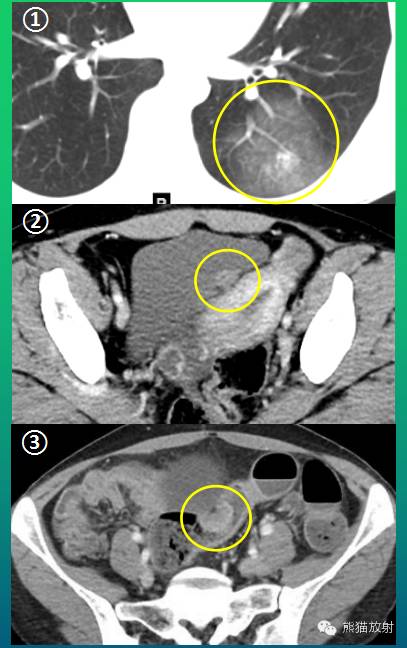

诸病灶分别如下图中圆圈所示:

女,39岁,下腹部阵发性疼痛2月余,大便次数增多,为粘液便,无便血、黑便。后患者腹痛反复发作,大便频繁。14余年前行剖宫产手术。

结肠镜检查:乙状结肠远端(距肛门约20cm)见粘膜广基隆起,表面充血、糜烂,周围粘膜蛇皮样变,至肠腔狭窄,取活检4块。病理示:(乙状结肠)粘膜糜烂性活动性炎症伴固有腺增生及灶性淋巴组织增生。

超声内镜检查:距肛门20cm见2.0cm的隆起,表面粘膜粗糙、糜烂。病灶呈低回声,内回声均质,边界清,大小约2.1*1.4cm,起源于固有肌层。

术后病理:(乙状结肠)子宫内膜异位症。